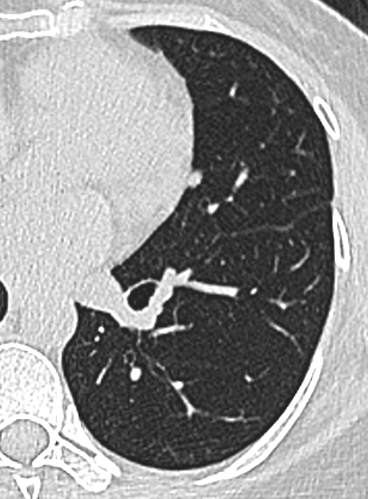

23年初复查CT左下肺GGO有所增大,直径:6.9mm

img

问题来了,一年多后复查GGO有增大,考虑恶性吗,需要手术吗,病理考虑什么?